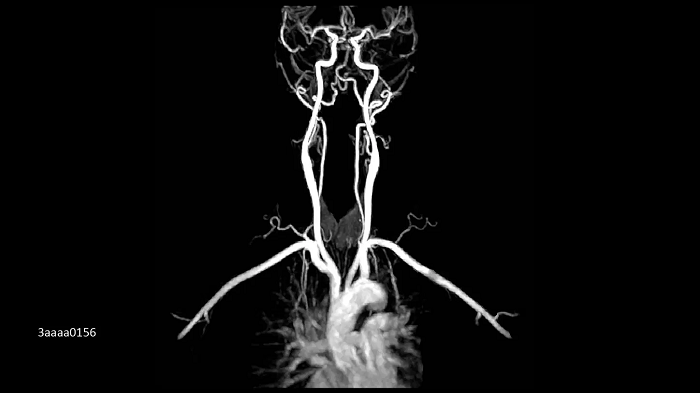

MR Angiography of the carotids.

- BioMatrix Spine 32

- BioMatrix Head/Neck 20

Image Credit: Siemens Healthineers